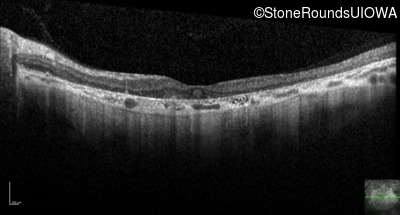

Optical Coherence Tomography - Right - 20/250 sc

Exemplar / OCT Stack

OCT Stack